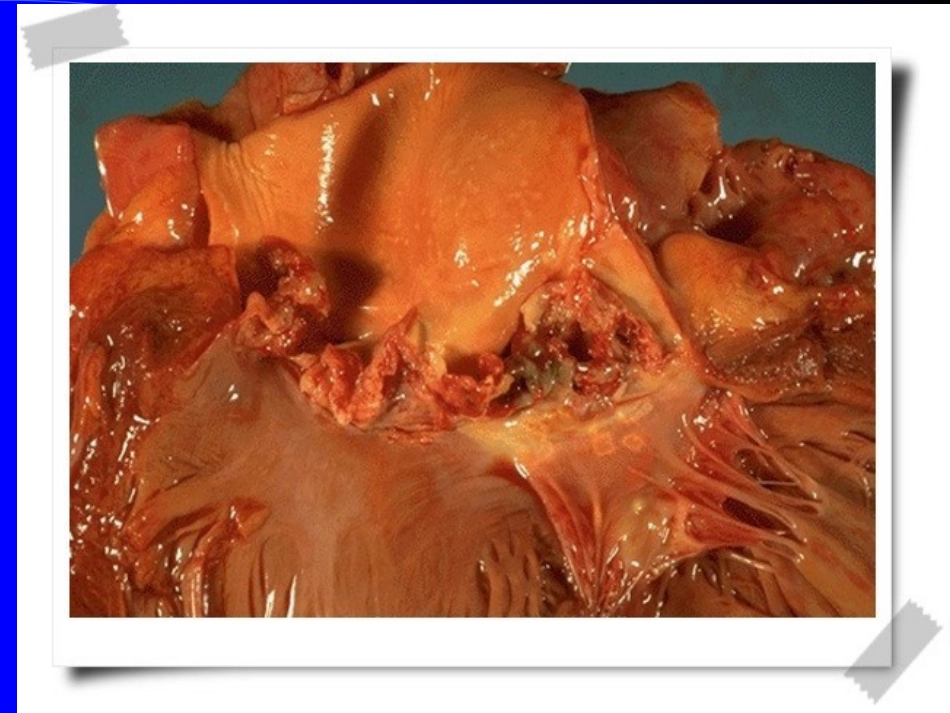

感染性心内膜炎感染性心内膜炎InfectiveEndocarditisInfectiveEndocarditis黔东南州人民医院心内科王芳感染性心内膜炎(感染性心内膜炎(IEIE)定义及分类)定义及分类特指心内膜的微生物感染,指发生于心脏各瓣膜、先天或后天性的病变处,心腔壁或人造瓣膜周围组织的微生物感染,伴赘生物形成。分类:病因:细菌性,衣原体性,霉菌性病程:急性、亚急性累及瓣膜性质:自体瓣膜(NVE),人工瓣膜(PVE)和药瘾者的心内膜。发病部位:左心IE,右心IE发病情况发病情况约占住院病人的1‰青年患者占多数,且男性病人较多有基础心脏病者多亚急性较急性多,约占2/3流行病学特点流行病学特点近年感染性心内膜炎发病率与以往相比无明显改变,但基础病因及致病病原体已发生了变化复杂的先心病和未行修补术的室间隔缺损是引起儿童感染心内膜炎最常见的心脏隐患新出现的院内心内膜炎:心血管介入,静脉高营养,起搏器,透折分流等自体瓣膜心内膜炎自体瓣膜心内膜炎病原学研究病原学研究主要致病菌为:链球菌,主要是草绿色链球菌(占30%-65%)、亚急性IE中70%-80%由其所致;葡萄球菌(占25%),急性IE中金葡菌超过50%混合感染:多见于人工瓣膜,近年自体瓣膜也常见霉菌性:近年明显增多,多见于人工瓣膜,静脉药瘾者其他病原微生物感染罕见亚急性发病机理亚急性发病机理血流动力学因素非细菌性血栓性心内膜病变(血小板聚集,结节样无菌性赘生物形成)病原微生物感染,短暂性菌血症)细菌感染无菌性赘生物菌血症菌血症病原微生物侵入血流导致菌血症是必要因素常是一过性,持续15-30分钟大多与医源性有关:据报道4%-49%的IE由介入操作引起;其他如拔牙,泌尿道及妇科等小手术,气管镜等器械检查外科感染静脉药物成瘾者心血管疾病与其他易患因素心血管疾病与其他易患因素主要是器质性心脏病及大血管疾病所具有的血流动力学改变,是IE发生、发展的基础常见病有:风心病,先心病,退行性心脏病,二尖瓣脱垂;心脏手术;人工瓣膜IEIE发病特点发病特点常累及的心瓣膜为二尖瓣,其次是主动脉瓣,三尖瓣及肺动脉瓣虽6%-24%IE有先心病基础,但房缺极少发生IE肥厚梗阻型心肌病伴压力梯度高的患者易发生IE二尖瓣脱垂伴返流及主动脉瓣退行性疾病是IE最常见的易患因素病源微生物感染环节病源微生物感染环节血流动力学改变导致心血管内膜的损害:存在血液返流;返流的血液通过狭窄的孔道;孔道两端腔道间有较高的压力差无菌性血栓性心内膜炎:内皮受损所致无菌性赘生物,病原微生物定居赘生物形成及细菌感染无菌性赘生物:与细菌数量及粘附力有关急性急性IEIE发病机理发病机理大多发生于正常瓣膜,约50%-60%菌血症大多为活动性感染病灶,常发生于败血症病程中病原毒力强大多没有无菌性血栓性心内膜炎过程临床表现临床表现IE临床表现复杂,可涉及所有器官感染的全身与局部作用心脏外的转移性感染动脉栓塞全身性免疫反应取决于病原微生物的性质临床表现及体征临床表现及体征发热:见于95%以上患者,为驰张热心脏杂音:见于90%患者,且杂音易变周围征:皮肤淤点,Osler小结(指、趾垫出现的痛性结节),Janeway斑(手掌、足底处无痛性出血红斑),Roth斑(视网膜的卵圆形出血斑,其中心成白色),甲下线状出血动脉栓塞:脾大:30%患者,与病程有关贫血:为轻、中度常见并发症常见并发症心脏:心衰(首位死亡原因),心肌脓肿,心包炎,心肌炎动脉栓塞:约5%-30%,见于任何器官组织细菌性动脉瘤:较少见,约3%-5%转移性感染:可在任何部位形成(金葡菌及念珠菌常见)神经系统:约30%;脑栓塞,脑膜炎,脑出血,细菌性动脉瘤,脑脓肿,癫痫样发作肾脏:肾动脉栓塞,肾炎,肾脓肿血培养是诊断血培养是诊断IEIE的重要依据的重要依据未经治疗亚急性患者,第一日间隔1h采血1次,其3次;如无细菌生长,第2日采血3次后,开始治疗已使用抗菌素者,停药2-7天,不发热时采血急性者,于1-2h内采2-3次血后开始治疗血标本量要足,必要时行特殊培养确诊IE,需同一病原体2次以上阳性结果免疫血清学检查免疫血清学检查免疫...